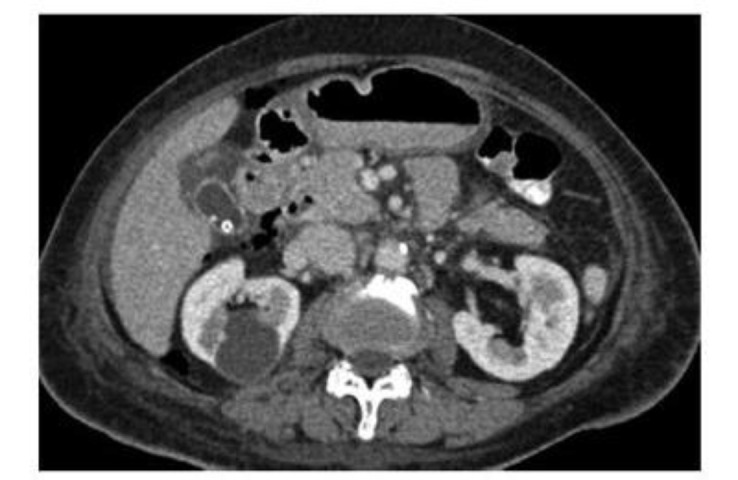

内镜逆行胰胆管造影(ERCP)已成为治疗胆道和胰腺疾病的基本治疗方式。然而,穿孔仍然是ERCP和内镜下括约肌切开术最令人担忧的并发症之一。ERCP术后穿孔的发生率相对较低,但相关死亡率可达7.8%。穿孔的诊断和处理取决于损伤的机制、位置和程度,正如临床和放射学所显示的那样。本文详细介绍了ercp相关穿孔的原因、分类、诊断、管理和预防策略。

Endoscopic retrograde cholangiopancreatography (ERCP) has become an essential treatment modality for managing biliary and pancreatic disorders. However, perforation remains one of the most concerning complications associated with ERCP and endoscopic sphincterotomy. While the incidence of perforation following ERCP is relatively low, the associated mortality rate can reach 7.8%. Diagnosis and management of perforations depend on the injury's mechanism, location, and extent, as clinical and radiographic findings suggest. This paper provides a detailed overview of the causes, classification, diagnosis, management, and prevention strategies for ERCP-related perforations.